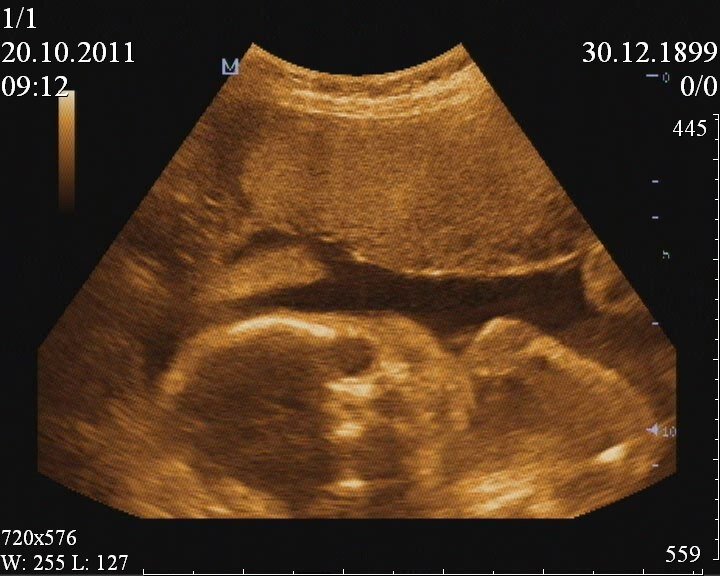

На первом скрининге врач, записав все параметры, повернула ко мне монитор и стала показывать ручки, ножки, пересчитала пальчики. И в конце предположила :"У вас девочка. Но пока что это не точно". На тот момент срок был 12 недель. Я понимала, что вероятность ошибки высока.

12 недель, рост 5 см)

В 16 недель меня снова направили на узи, пошла вместе с мужем.И нам в очередной раз подтвердили девочку.

16 недель.